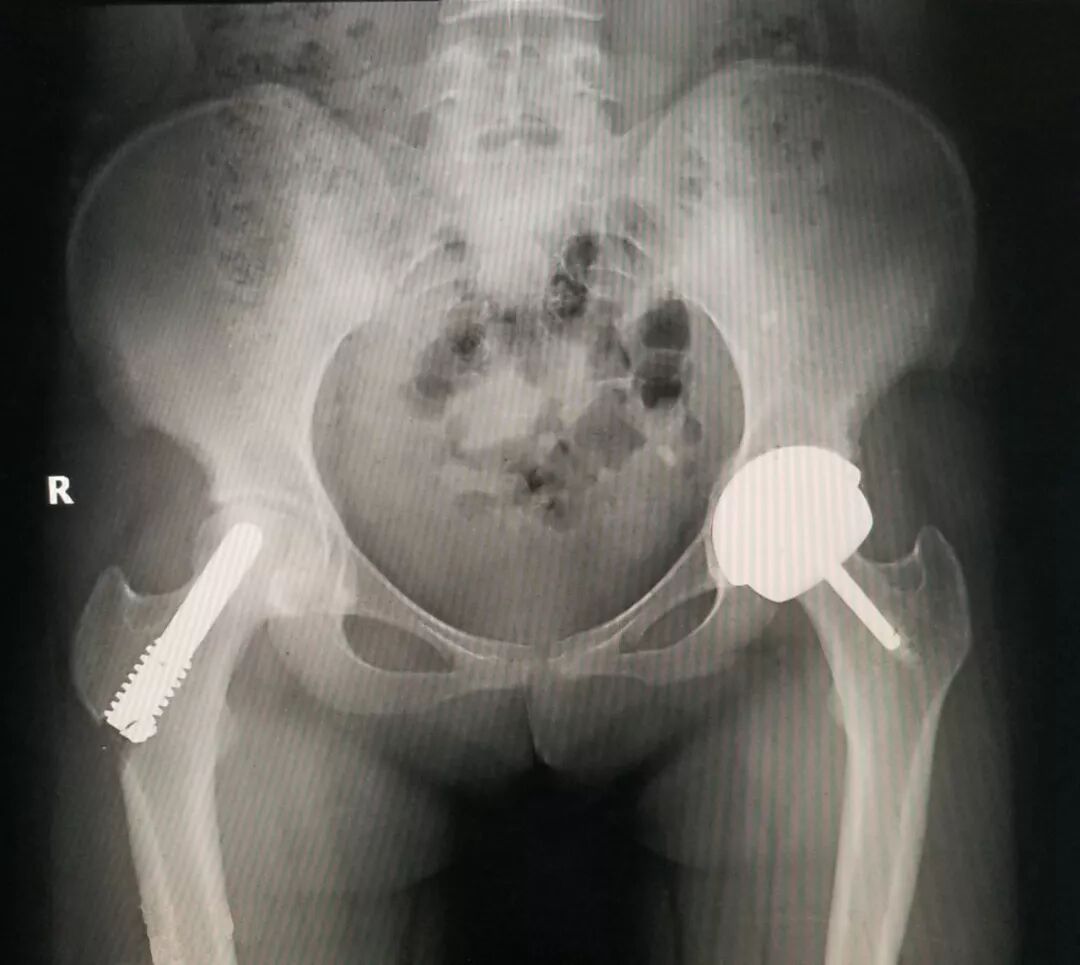

患者張阿姨,51歲,因髖部疼痛就診于省級知名骨科專家、邦爾骨科集團首席專家、嘉興邦爾骨科醫(yī)院院長趙凱專家門診。

根據(jù)病史及患者體格檢查的相應(yīng)癥狀,考慮患者為左側(cè)股骨粗隆間病理性骨折,屬于原發(fā)性疾病導(dǎo)致的骨轉(zhuǎn)移。趙凱教授為其進行了“左側(cè)股骨粗隆病理性骨折病灶清除術(shù)+截骨術(shù)+人工髖關(guān)節(jié)置換術(shù)+左外髖外展肌群重建術(shù)”。術(shù)后患者病情穩(wěn)定,恢復(fù)良好。

與普通髖關(guān)節(jié)置換不同的是,對于這一例關(guān)節(jié)置換手術(shù),醫(yī)生采用了特殊的人工關(guān)節(jié)系統(tǒng)——組配式關(guān)節(jié)假體。它是專門適用于股骨近端腫瘤、粉碎性骨折、翻修等其他原因所致的股骨近端骨質(zhì)缺損這些疾病。假體各個組件之間可任意組配,術(shù)中可以根據(jù)截骨長度靈活安裝。

術(shù)前顯示:左側(cè)髖關(guān)節(jié)被腫瘤侵蝕嚴(yán)重

術(shù)后假體位置良好